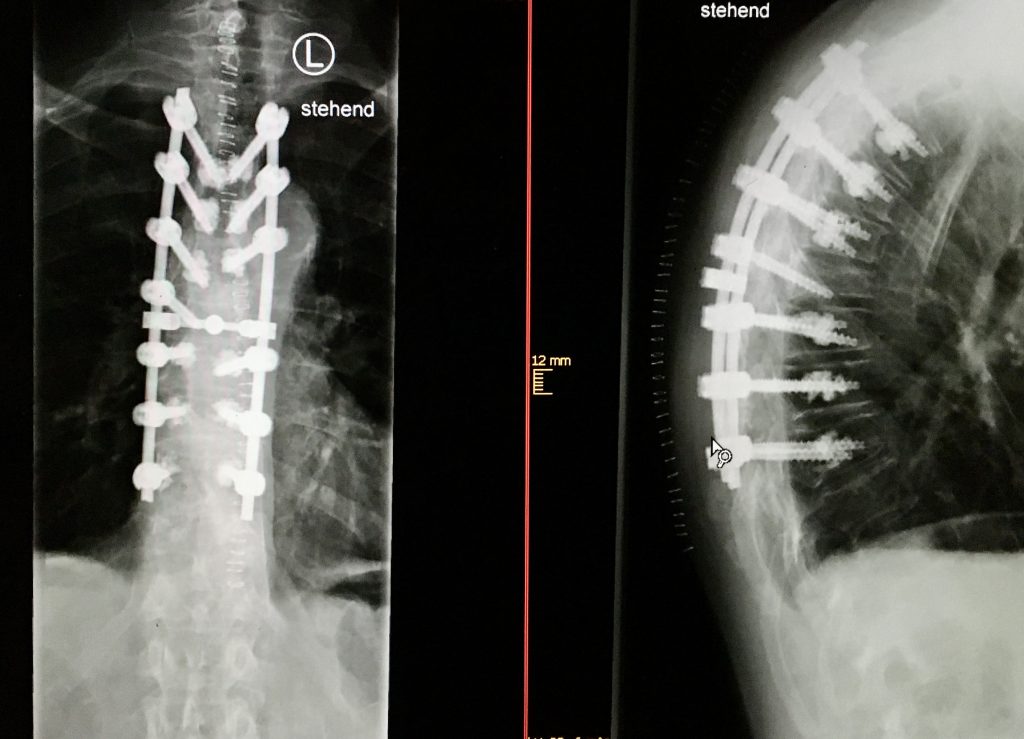

Habitualmente la escoliosis se corrige por vía posterior con monitorización de la función nerviosa durante la intervención (neurofisiología intraoperatorios). Se colocan tornillos en las vértebras y se acoplan con barras de metal a cada lado de la columna, tras realizar las maniobras de corrección necesarias, se consigue de este modo estabilizar el raquis y una columna vertebral más equilibrada y de aspecto más recta. Lo más habitual es utilizar técnicas de fusión ósea mediante el aporte de injerto de hueso del propio paciente o material sustitutivo al lecho quirúrgico. Este proceso se denomina fusión espinal. Las barras de metal acopladas a la columna vertebral aseguran que la columna permanezca recta mientras se produce la fusión espinal.